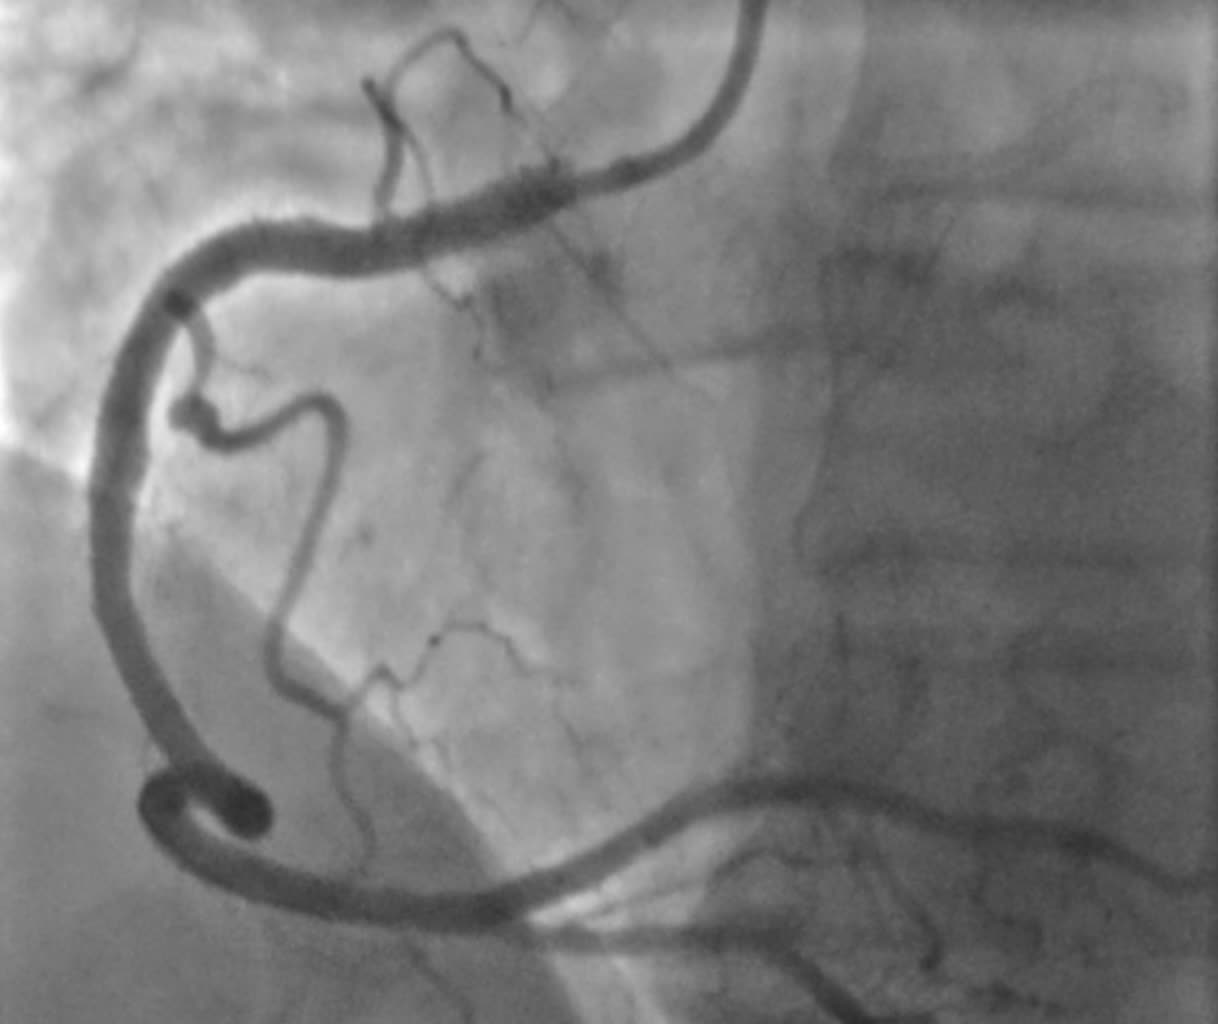

W pracowni radiologii zabiegowej Szpitala Specjalistycznego Ducha Świętego w Sandomierzu wykonano prekursorski zabieg z użyciem minimalnej objętości kontrastu w trakcie angioplastyki wieńcowej czyli naprawy zwężeń w tętnicach wieńcowych u pacjenta z chorobą wieńcową. W zabiegu brali udział lekarze Michał Tarnowski, Mateusz Wiśniowski, Paweł Konrad i dr n. med. Piotr Wańczura.

Zabiegi takie wykonuje niewiele ośrodków. Pomagają one ochronić pacjentów jeżeli chodzi o uszkodzenie funkcji nerek.

Fot. Szpital Specjalistyczny Ducha Św. w Sandomierzu/Facebook